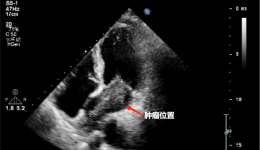

突然“咯血”!气管被堵!茂医MDT“软硬兼施”打通生命气道

提起咯血,相信大家第一反应都是影视剧中的人物在病入膏肓之时,撕心裂肺地咳嗽一场后,一口鲜血从口中喷涌而出......这种影视场面看多了,大家就会觉得一旦咯血,就预示着此人将命不久矣,因此对咯血非常害怕紧张。“医生,我最近突然咯血了怎么办...